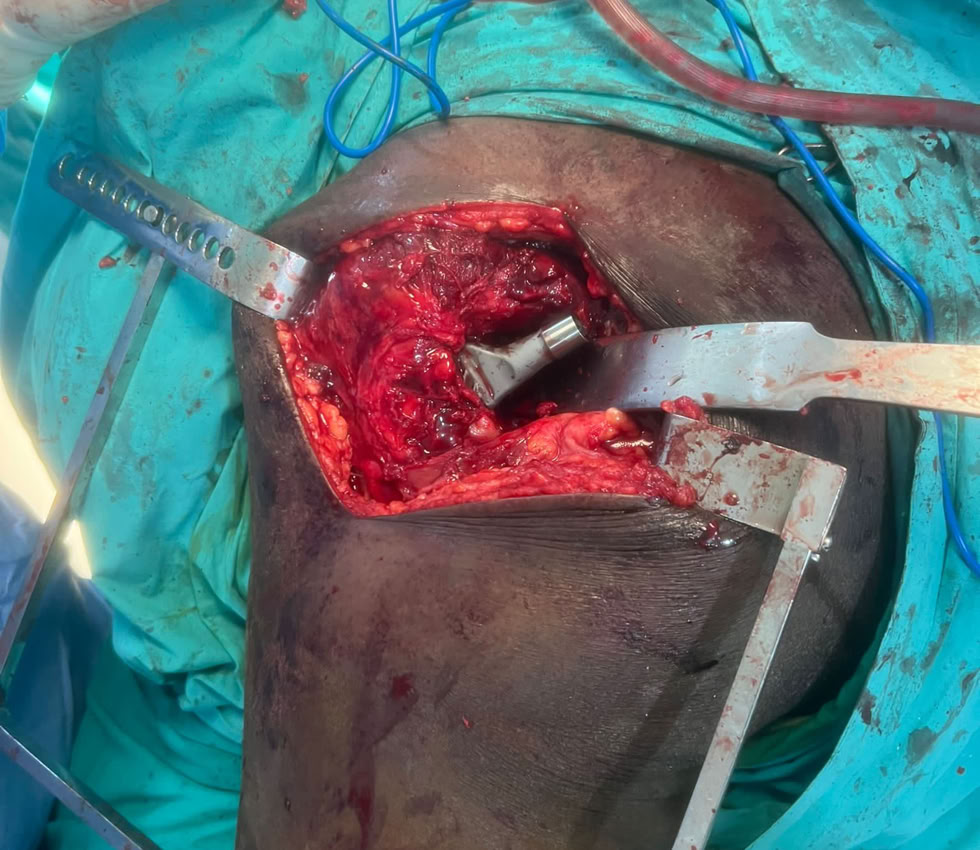

Nada mas llegar, fractura de fémur y tibia abiertas . Dos magníficas traumatólogas, una enfermera excepcional y una anestesista fuera de serie, resolvieron la urgencia.

Y el domingo empezamos la tarea operando una fractura diafisaria de fémur y una fractura de tobillo (Pilón tibial). De esta manera hemos podido estrenar el nuevo equipo de Rx del quirófano que es un móndelo mas avanzado que el que teníamos hasta ahora. Una maravilla de equipo.

Gran carga de trabajo por las múltiples fracturas que hemos atendido, pero también hemos tenido tiempo de hacer una Prótesis Total de Cadera,  a un paciente de 71 años con una Necrosis Avascular de Cabeza Femoral . Le hemos mejorado la calidad de vida, ya que estaba prácticamente inválido y aquí podemos ver como se maneja caminando a las 48 h de la intervención